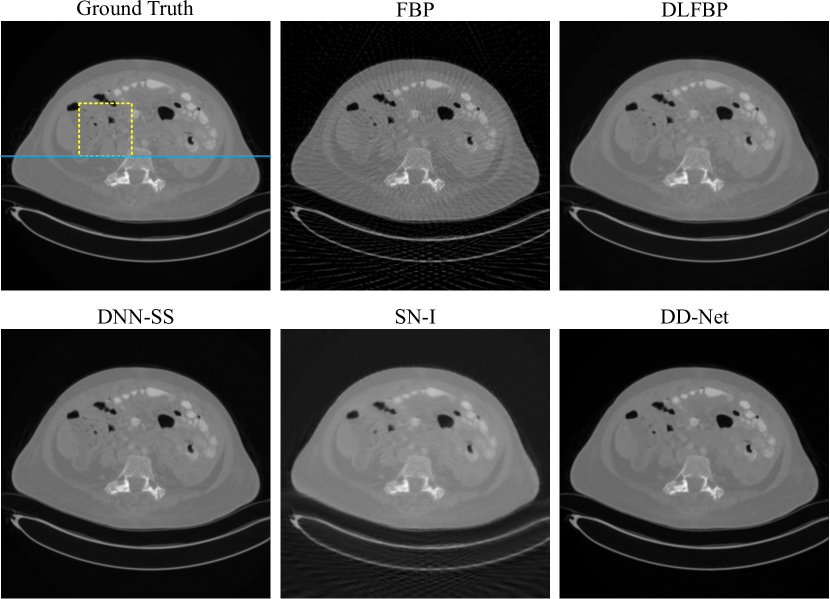

Figs.4-6 present results of one of the 100 synthetic phantoms with 120 views for testing using different methods. Same regions indicated with yellow box are enlarged for better visualization in Fig.5. The image intensity profile in same position is shown in Fig.6.

As expected, severe artifacts exist in the result using FBP, and DLFBP, DNN-SS, SN-I and DD-Net could reduce the artifacts. Though most artifacts are suppressed, there still remains some in the background using SN-I, furthermore, its central part of the image has the clearest structure and the nearer the boundary, the more blurred it is. DD-Net could also remove the artifacts satisfactorily, but the result is overly smoothed, and there is slight distortion in the edge structure. As shown in Fig.5 and Fig.6, DD-Net loses small image details and the pixel value changes gently and far from the reference value. Through visual inspection, DLFBP and DD-Net could remove the artifacts and retain small structures.

Refer to caption

Figure 4: One group of results from synthetic data sets with incomplete phase-contrast sinogram of 120 views, using FBP, DLFBP, DNN-SS, SN-I and DD-Net. Same regions of these images, indicated by yellow box, are enlarged for better visualization.

Figure 5: Enlarged regions indicated by yellow box in Fig.4 for better visualization. DLFBP and DNN-SS could remove the artifacts and retain small image structures.